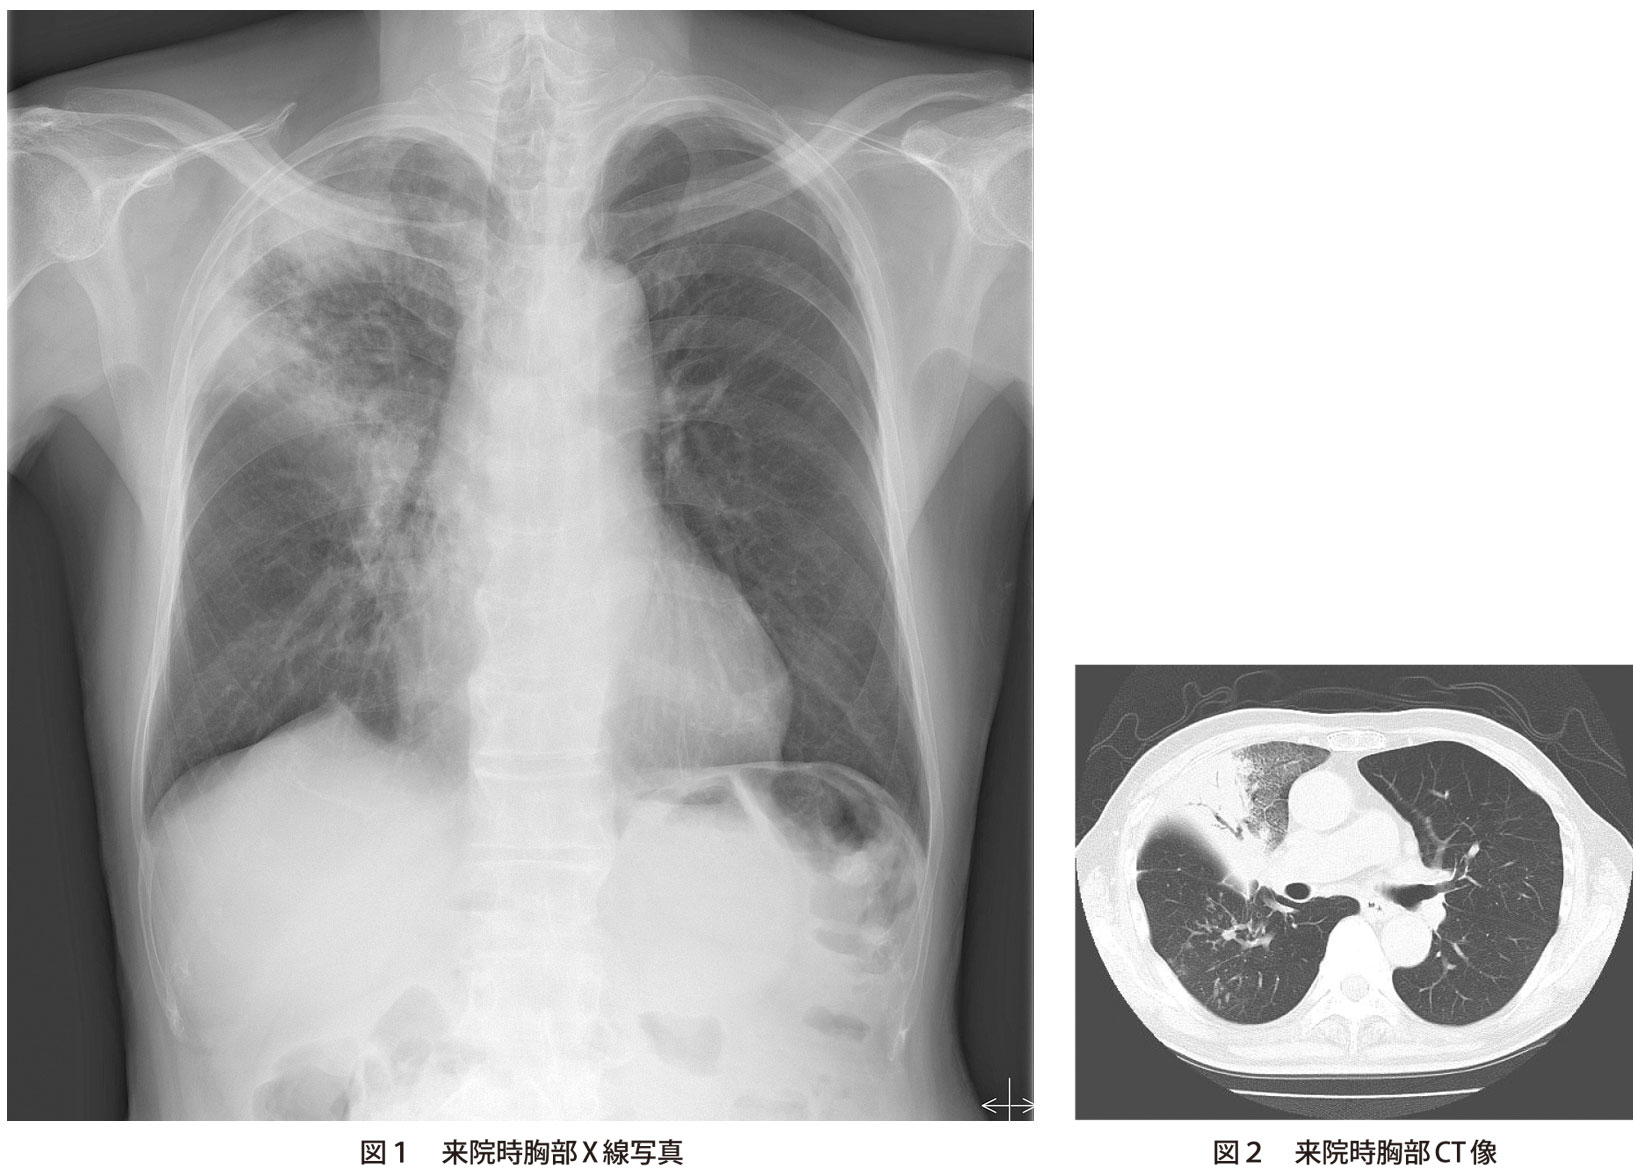

市中肺炎の画像 ―画像所見から原因微生物は推定可能か? 宮下 修行 黒瀬 浩史 岡 三喜男 Keywords:市中肺炎,胸部画像,肺炎球菌,マイコプラズマ,レジオネラ 〔日内会誌 99:1097~1103,10〕 1.抗菌薬選択からみた原因微生物の分類. 4mバイトの画像を伝送するとき,1秒間に 伝送できる最大の画像枚数はどれか。 2 1. レジオネラ肺炎の画像診断 東京都立駒込病院放射線診断部医長 酒井 文和 はじめに 本日はレジオネラ肺炎の画像所見の特徴についてお話したいと思います。 ご存じのように、レジオネラ肺炎は、いわゆる異型肺炎の一形で、通常のβ-lactam 系の.

レジオネラ肺炎 画像では従来から肺胞性肺炎を呈するとさ れてきた。 近年の報告では、非区域性に分布するすり ガラス陰影に混在して、気管支血管束周 囲に分布する境界明瞭なコンソリデーショ ンが認められることが特徴であるとされて いる。. Pseudopneumoniae 以外は全て陰性判定となった。(菌濃度: 2.0×108 CFU/mL). High-resolution computed tomography is useful for early diagnosis of severe acute.